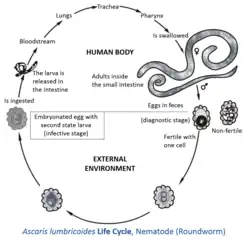

Life cycle

Ascaris lumbricoides, a roundworm, infects humans via the fecal-oral route. Eggs released by adult females are shed in feces. Unfertilized eggs are often observed in fecal samples but never become infective. Fertilized eggs embryonate and become infectious after 18 days to several weeks in soil, depending on the environmental conditions (optimum: moist, warm, shaded soil).[5]

Infection occurs when a human swallows water or food contaminated with embryonated eggs. In the duodenum, a single rhabditiform larva hatches from each of the ingested eggs. The larvae then penetrate the mucosa and submucosa and enter the venules or lymphatic vessels. From there, the larvae then pass through the heart to enter the pulmonary circulation. The larvae then break through the walls of the pulmonary capillaries to enter the alveoli.[6][7] The juvenile worms then migrate from the alveoli, through the bronchioles and bronchi, and into the trachea. An acute inflammatory reaction can occur if some of the worms get lost during this migration process and accumulate in other organs of the body.[7]

Once in the trachea, the worms are coughed up into the pharynx and then swallowed again, after which they pass through the stomach and into the small intestine, where they mature into adult worms.[5][7] The adult worms begin producing fertilized eggs within 60–65 days of being swallowed;[7] females produce as many as 200,000 eggs per day for 12–18 months. These fertilized eggs become infectious after two weeks in soil; they can persist in soil for 10 years or more.[6]

It might seem odd that the worms end up in the same place where they began. One hypothesis to account for this behavior is that the migration mimics an intermediate host, which would be required for juveniles of an ancestral form to develop to the third stage. Another possibility is that tissue migration enables faster growth and larger size, which increases reproductive capacity.[7] The eggs have a lipid layer which makes them resistant to the effects of acids and alkalis, as well as other chemicals.[8]